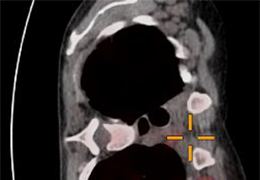

ANYTHINK 经导管主动脉瓣膜置换术分析系统